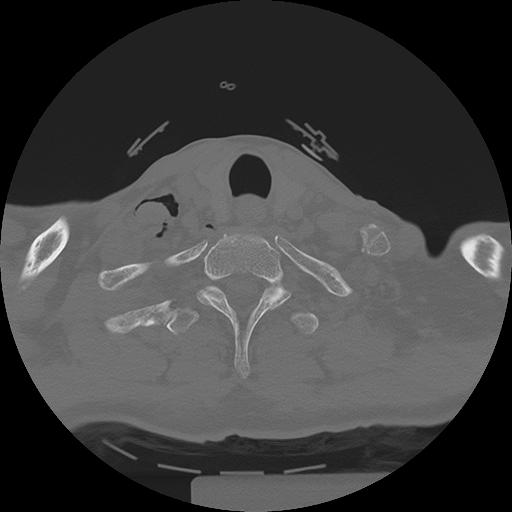

11 HUESO,,Axial,2.0,HUESO,,